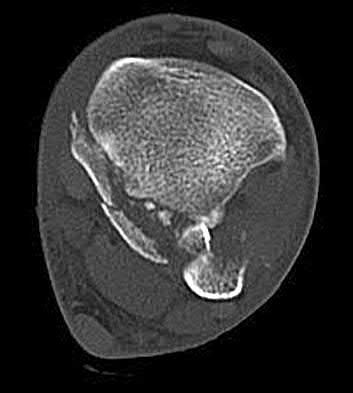

Question 12:

A 55-year-old patient presents with a slowly enlarging, painful mass in the proximal humerus. Biopsy reveals a hyaline cartilage matrix with cellular atypia, confirming a diagnosis of central conventional chondrosarcoma. Which of the following genetic mutations is most frequently identified in this specific tumor?

Correct Answer: IDH1 / IDH2

Explanation:

Mutations in the isocitrate dehydrogenase genes, IDH1 and IDH2, are found in up to 50-60% of central conventional chondrosarcomas and enchondromas. EXT1 and EXT2 mutations are characteristic of multiple hereditary exostoses (osteochondromas). GNAS mutations are seen in fibrous dysplasia. TP53 and RB1 mutations are hallmark aberrations in osteosarcoma.